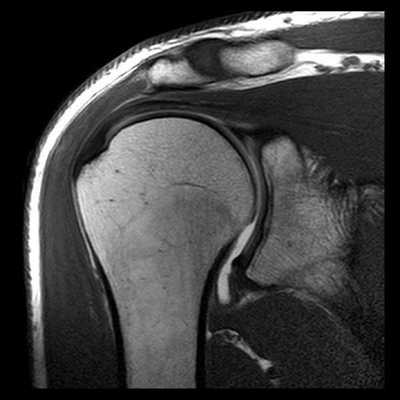

МРТ артрограмма при отведении и наружной ротации в плечевом суставе в норме

Первая из 24 последовательных Т1-взвешенных МР-томограмм правого плечевого сустава в косой продольной проекции с направлением срезов от медиальной стороны к латеральной. Томограммы получены с использованием плечевой катушки на 3Т МР-томографе. В наиболее медиальный срез попадает латеральный отдел легкого и грудная стенка. Широчайшая мышца спины покрывает нижнюю поверхность большой круглой мышцы. Эти мышцы сложно различить как отдельные структуры. Обе мышцы проходят в верхнелатеральном направлении и прикрепляются к гребню малого бугорка. К мышцам вращательной манжеты плеча относятся надостная, подостная, малая круглая и подлопаточная. Все мышцы вращательной манжеты начинаются от лопатки. Лопаточно-подъязычная мышца начинается от верхнего края лопатки. Она состоит из верхнего и нижнего брюшек. Верхнее брюшко прикрепляется к нижнему краю подъязычной кости. Лопатка имеет Y-образную форму вследствие наличия направленной кзади ости лопатки. В норме надостная мышца полностью находится внутри «Y» и заполняет весь ее объем, если не развивается атрофия мышцы. У верхней поверхности плечевого сустава можно увидеть часть трапециевидной мышцы. Трапециевидная мышца прикрепляется к верхнему краю латерального отдела ключицы, медиальному краю акромиона и верхнему краю ости лопатки. Дельтовидная мышца прикрепляется к тем же костным структурам рядом с трапециевидной мышцей, только к противоположной стороне каждой из костей (нижнему краю латерального отдела ключицы, латеральному краю акромиона и нижнему краю ости лопатки). Подлопаточная мышца заполняет подлопаточную ямку лопатки. Подостная и малая круглая мышцы расположены ниже ости лопатки. Подостная мышца крупнее и лежит выше малой круглой мышцы. Надостная, подлопаточная, малая круглая и подостная мышцы (по часовой стрелке) продолжаются в латеральном направлении. Сухожилия подостной и надостной мышц соединяются у латеральной поверхности головки плечевой кости. Ость лопатки заканчивается у акромиального отростка. Начинает визуализироваться акромиально-ключичный сустав. Сосудисто-нервный пучок проходит вдоль передней поверхности подлопаточной мышцы. Срез на уровне суставной впадины лопатки. Виден темный край проходящей по окружности суставной губы. От клювовидного отростка начинаются клювовидно-плечевая мышца и сухожилие короткой головки двуглавой мышцы. Суставно-плечевые связки визуализируются в виде пучков ткани с низкой интенсивностью сигнала, окружающих переднюю, нижнюю и задненижнюю поверхности плечевого сустава. Суставно-плечевые связки укрепляют капсулу сустава. Срез на уровне медиального края головки плечевой кости. Задняя артерия, огибающая плечевую кость, огибает шейку плечевой кости и анастомозирует с передней одноименной артерией. Вращательный интервал представляет собой треугольное пространство, ограниченное сверху передним краем сухожилия надостной мышцы, снизу—верхней поверхностью сухожилия подлопаточной мышцы, с медиальной стороны—основанием клювовидного отростка, а с латеральной стороны—сухожилием длинной головки двуглавой мышцы в межбугорковой борозде. Сухожилие длинной головки двуглавой мышцы начинается от над-суставного бугорка у верхнего края суставной впадины. На этом изображении оно проходит в дистальном направлении над головкой плечевой кости, окруженное синовиальной оболочкой. Сухожилие прободает капсулу сустава через отверстие, расположенное около межбугорковой борозды. На уровне середины головки плечевой кости дельтовидная мышца покрывает наружную поверхность плечевого сустава. Оценивать морфологический тип акромиального отростка лучше всего на первом срезе латеральнее акромиально-ключичного сустава. Вращательная манжета на уровне латеральной поверхности головки плечевой кости состоит преимущественно из сухожилий. Сухожилия начинают срастаться друг с другом и суставной капсулой. Уровень срезов приближается к латеральной поверхности головки плечевой кости. Сухожилия вращательной манжеты образуют непрерывный ободок тканей над головкой плечевой кости, а затем продолжаются в латеральном направлении. На этой Т1-взвешенной томограмме сигнал от сухожилий вращательной манжеты имеет более высокую интенсивность вследствие развития феномена «магического угла», в отличие от низкой интенсивности сигнала от сухожилий в норме. Нормальный сигнал от сухожилий можно увидеть при получении томограмм в режимах с большим эхо-временем. Сухожилия вращательной манжеты приближаются к месту прикрепления в области большого и малого бугорков. Сухожилие подлопаточной мышцы прикрепляется к малому бугорку и образует крышу межбугорковой борозды. Сухожилия надостной, подостной и малой круглой мышц прикрепляются к большому бугорку — к верхней, средней, и нижней поверхностям соответственно. Все еще видно прикрепление небольшой части пучков надостной и подостной мышц к большому бугорку. Наиболее латеральная поверхность плечевого сустава полностью покрыта средними пучками дельтовидной мышцы.